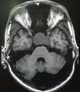

Sellar lesion

A Rathke's cleft cyst is a benign growth on the pituitary gland in the brain, specifically a mucin-filled cyst in the posterior portion of the anterior pituitary gland. It occurs when the Rathke's pouch does not develop properly and ranges in size from 2 to 40 mm in diameter.Asymptomatic cysts are commonly detected during autopsies in 2 to 26 percent of individuals who have died of unrelated causes. [Source: Wikipedia ]